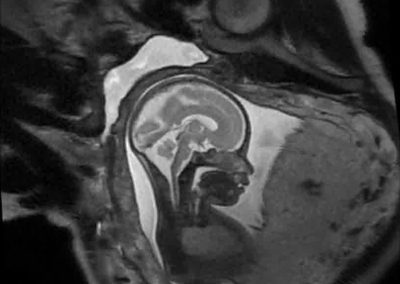

L’Université Paris Cité franchit une nouvelle étape dans le domaine de l’imagerie médicale anténatale avec l’acquisition d’un système d’Imagerie par Résonance Magnétique (IRM) 1,5T ARTIST™ de GE HealthCare. Cet équipement de pointe renforce les capacités de la Plateforme LUMIERE à l’hôpital Necker-Enfants malades, plateforme intégrée de soins, de recherche clinique et d’enseignement en imagerie médicale de la femme enceinte, du fœtus et du placenta.

Une plateforme au service de la recherche et des patientes enceintes

Depuis 2020, la Plateforme LUMIERE offre aux femmes enceintes volontaires, entre 16 et 36 semaines d’aménorrhée et suivies à l’hôpital Necker-Enfants malades, la possibilité de participer activement à l’avancée de la recherche en médecine fœtale, tout en bénéficiant d’une IRM fœtale au cours de leur grossesse, réalisée dans un cadre sécurisé et encadré.

L’inclusion de ces patientes, depuis leur accueil jusqu’à la réalisation des examens d’imagerie, puis l’analyse des images et l’interprétation des résultats par des équipes expertes, enrichit une base de données structurée, unique au monde, au service de la recherche et de l’innovation en imagerie anténatale et en médecine fœtale.